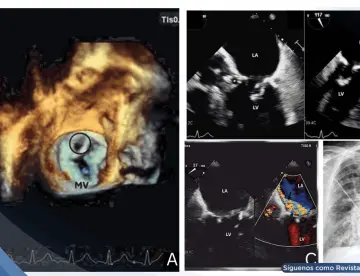

<content:encoded><![CDATA[<div><img src="https://blob.medicinaysaludpublica.com/images/2026/03/28/sacs-20--1146-10acbe5a-focus-0-0-360-276.webp" alt="Más de 8,000 casos confirmados de hipertensión pulmonar en Puerto Rico: Cifra real podría cuadruplicarse" title="Más de 8,000 casos confirmados de hipertensión pulmonar en Puerto Rico: Cifra real podría cuadruplicarse"></div><p>La <strong><a href='https://medicinaysaludpublica.com/tags/hipertension/13040' target='_blank'>hipertensión</a></strong> <strong><a href='https://medicinaysaludpublica.com/tags/pulmonar/45862' target='_blank'>pulmonar</a></strong>, una enfermedad que eleva la presión en las arterias de los <strong><a href='https://medicinaysaludpublica.com/tags/pulmones/13466' target='_blank'>pulmones</a></strong> y puede derivar en <strong><a href='https://medicinaysaludpublica.com/tags/fallo/52793' target='_blank'>fallo</a></strong> <strong><a href='https://medicinaysaludpublica.com/tags/cardiaco/33277' target='_blank'>cardíaco</a></strong> crónico, afecta a miles de puertorriqueños, muchos de ellos sin diagnóstico.&nbsp;</p>

<p>Así lo advirtió el Dr. Vinicio de Jesús, vicedecano de admisiones y profesor de medicina de la Universidad de Stanford, en entrevista exclusiva con la Revista Medicina y Salud Pública, durante la Conferencia Educativa de la Asociación de <strong>Hipertensión</strong> <strong>Pulmonar</strong>, capítulo de Puerto Rico.</p>

<p>Un estudio reciente identificó más de 8,000 casos de <strong>hipertensión</strong> <strong>pulmonar</strong> diagnosticados y confirmados en Puerto Rico. Sin embargo, el Dr. de Jesús advierte que ese número representa apenas una fracción del problema real.</p>

<p>"Si consideramos que en la población mundial hay un millón de <strong>pacientes</strong> con esta condición y consideramos que en Puerto Rico hay 3.2 millones de personas, conservadoramente podemos decir que pueden haber hasta 32,000 <strong>pacientes</strong> que todavía no hemos identificado", señaló el especialista.</p>

<strong>¿Qué es y por qué es peligrosa?</font></strong></h2>

<p>A diferencia de la <strong>hipertensión</strong> arterial común —aquella que se mide con el esfigmomanómetro—, la <strong>hipertensión</strong> <strong>pulmonar</strong> afecta específicamente el sistema vascular de los <strong>pulmones</strong>, que normalmente opera bajo baja presión.</p>

<p>"Cuando sube la presión dentro de los <strong>pulmones</strong>, el problema es que el <strong><a href='https://medicinaysaludpublica.com/tags/corazon/12206' target='_blank'>corazón</a></strong> derecho tiene problemas en mover sangre a los <strong>pulmones</strong>", explicó De Jesús. "Eventualmente el lado derecho del <strong>corazón</strong> no puede lidiar con esas altas presiones y el paciente desarrolla <strong>fallo</strong> <strong>cardíaco</strong> crónico."</p>

<p>Los síntomas incluyen fatiga, dolor en el pecho y edema en las extremidades, un cuadro clínico que puede confundirse con otras condiciones cardíacas y que contribuye al subdiagnóstico.</p>